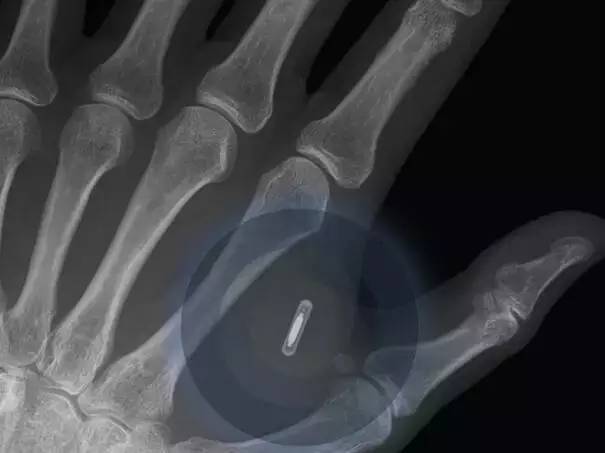

人类将可以在2023年将智能手机植入人体内。大约80%的被调查者预言在未来的7年内,人体内植入智能手机将可以用于商业。

而这种技术也能更准确地监控人们的身体健康情况,使人类在通过脑电波沟通方面又前进了一步。

植入式健康监控设备,比如计步器和人工耳蜗已经成为这类技术的主流,但是更多的植入式技术会在2025年之前与人们见面。